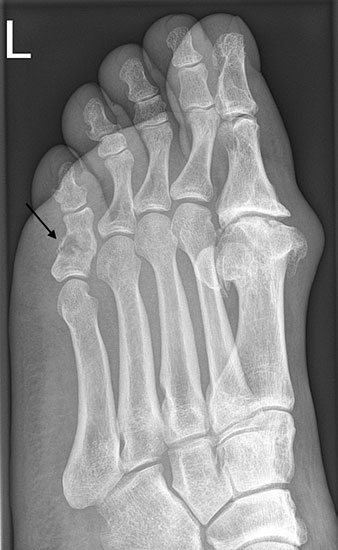

Das Enchondrom ist der häufigste Knochentumor im Bereich von Hand und Fuß und nach dem Osteochondrom der zweithäufigste gutartige Knochentumor überhaupt. Die geschlechtliche Verteilung ist ausgeglichen, Enchondrome finden sich meist bei Patienten zwischen 20-40 Jahren. Dieser chondrogene Tumor verhält sich meist asymptomatisch, kann aber durch eine Knochenexpansion und Schwellung sowie Spontanfrakturen (Abb. 17) auffallen. Radiologisch zeigen sich in der Regel gut abgrenzbare Osteolysen, Matrixverkalkungen sind typisch aber nicht obligat. Die MRT zeigt typischerweise eine annähernd flüssigkeitsäquivalente Signal­qualität mit niedrigen Signalintensitäten in T1 und hoher Signalgebung in T2, die Binnen­struktur weist eine für chondrogene Tumoren typische Lobulierung mit KM-Aufnahme auf.

Im Gegensatz zu Osteochondromen ist die Lage von Enchondromen nicht auf die Metaphyse beschränkt. Sie finden sich auch im Bereich der Epi- und Diaphysen. Die kurzen tubulären Knochen der Metatarsalia und Phalangen sind bevorzugt betroffen. Hier findet sich die Läsion typischerweise im Bereich der proximalen Phalangen oder distalen Metatarsalia, eine Ausbreitung auf die gesamte Diaphyse ist von hier aus jedoch nicht ungewöhnlich. Die Möglichkeit einer malignen Entartung (Chondrosarkom) ist im Bereich der Metatarsalia und Phalangen im Vergleich zu den langen Röhrenknochen und platten Knochen extrem selten 33. Die übliche Therapie besteht in einer gründlichen Curettage. Je nach Größe des Defekts und Schwächung der Kortikalis kann die Transplantation eines stabilisierenden kortiko­spongiösen Spans notwendig werden. Zusätzliche osteosynthetische Verfahren sind nur selten erforderlich.